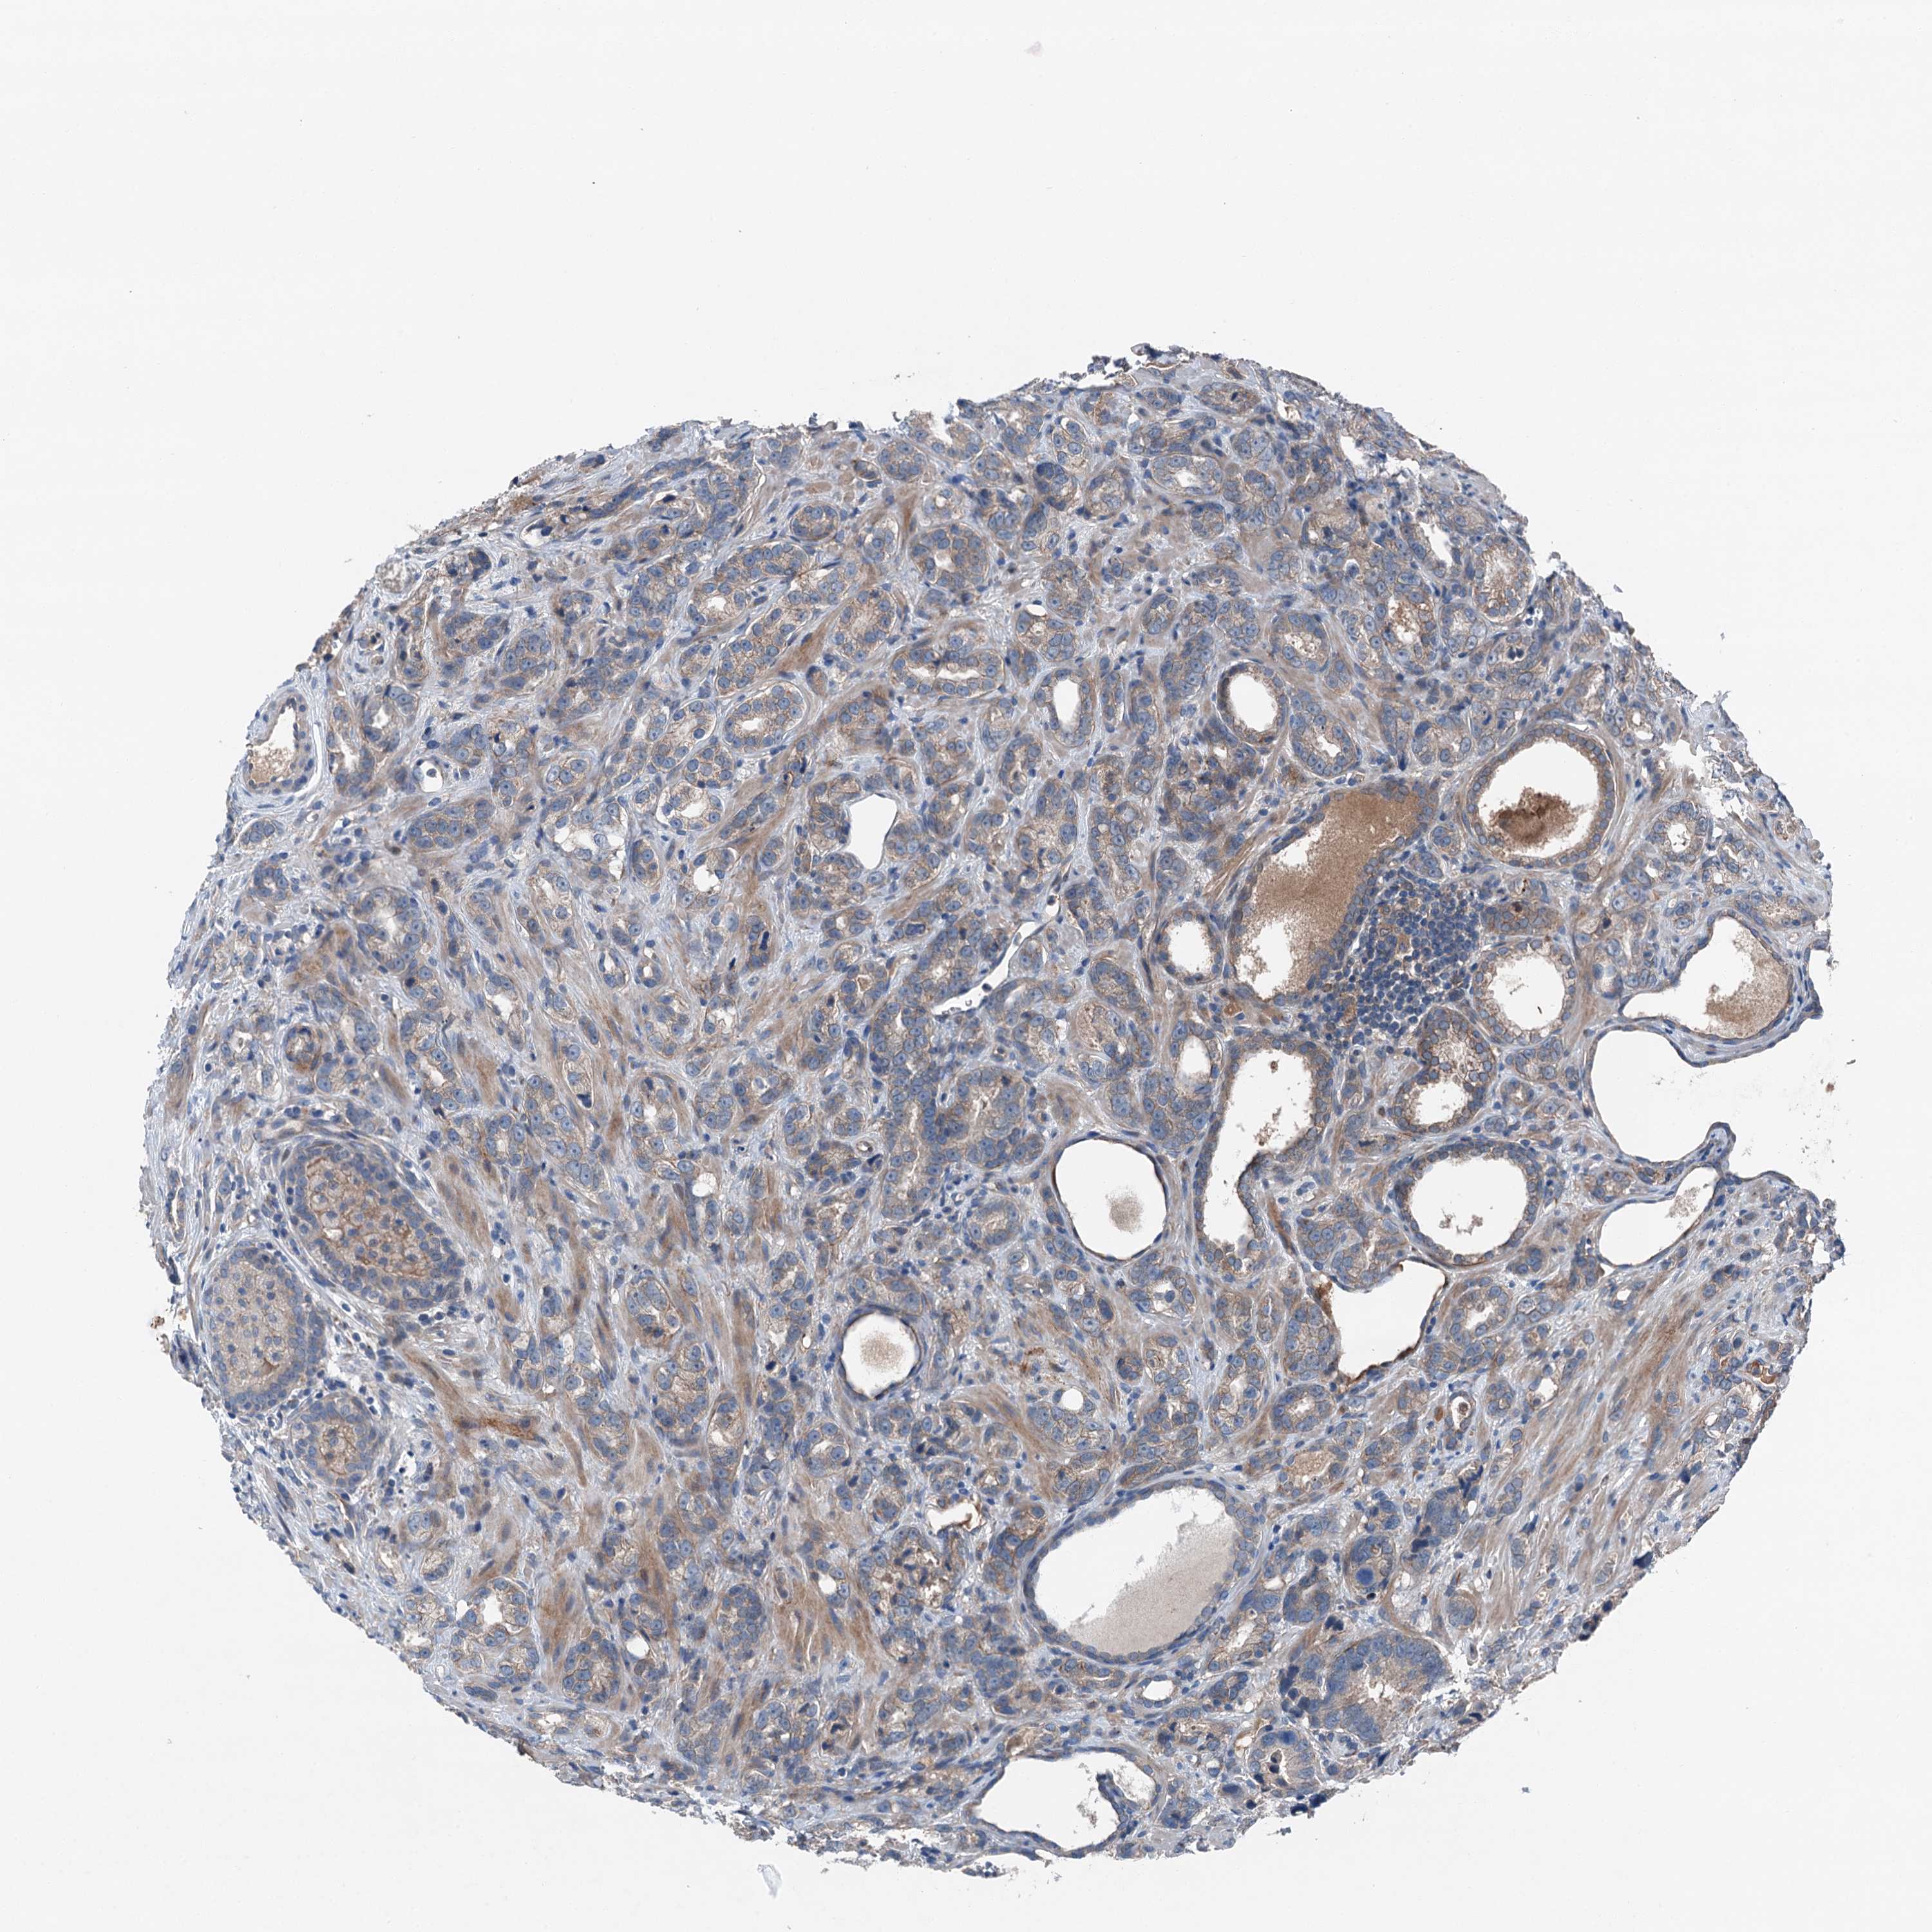

PROSTATE CANCER - Protein expressioni

A mouse-over function shows sample information and annotation data. Click on an image to view it in a full screen mode. Samples can be filtered based on level of antibody staining by selecting one or several of the following categories: high, medium, low and not detected. The assay and annotation is described here.

Note that samples used for immunohistochemistry by the Human Protein Atlas do not correspond to samples in the TCGA dataset.

Antibody stainingi

Antibody staining in the annotated cell types in the current human tissue is reported as not detected, low, medium, or high, based on conventional immunohistochemistry profiling in selected tissues. This score is based on the combination of the staining intensity and fraction of stained cells.

Each image is clickable and will lead to virtual microscopy that enables deeper exploration of all samples and also displays staining intensity scores, fraction scores and subcellular localization as well as patient and tissue information for each sample.

Antibody HPA041015

Staining

High

Medium

Low

Not detected

Intensity

Strong

Moderate

Weak

Negative

Quantity

>75%

75%-25%

<25%

None

Location

Nuclear

Cytoplasmic/membranous

Cytoplasmic/membranous,nuclear

Adenocarcinoma, High grade

Adenocarcinoma, Low grade